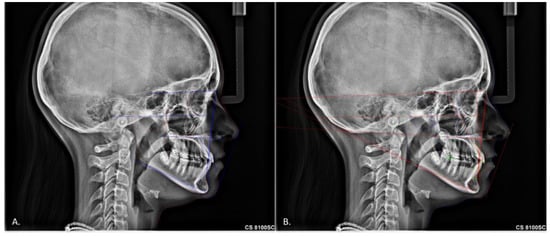

Comparing a Fully Automated Cephalometric Tracing Method to a Manual Tracing Method for Orthodontic Diagnosis

2. Materials and Methods